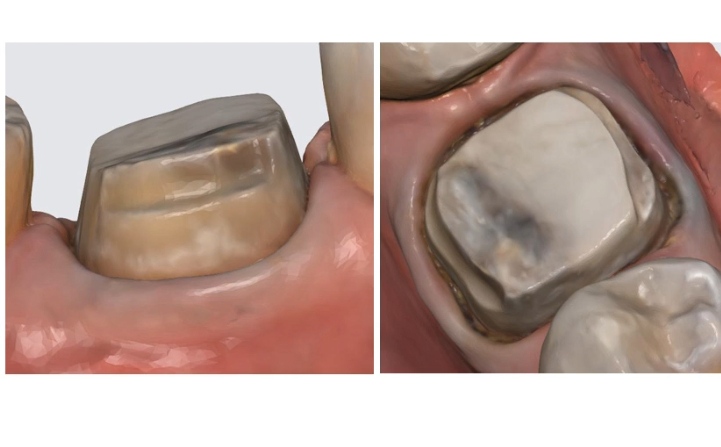

5- Edgeless and Shoulderless

7- Inverted Shoulder

13- Prosthetic Space

14- Thickness and Material Of The Crowns